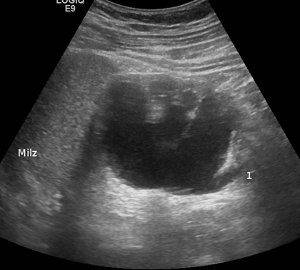

Визуализационный метод в анатомических структурах проводят при введении контрастных веществ в мочевые пути. Также выполняется рентгеновский снимок после небольшого промежутка времени, как ввели внутривенный инъекционный раствор.

image

У внутривенной урографии есть ряд особенностей:

• при помощи рассматриваемого метода определяется полная морфологическая картина сформировавшегося расстройства в органе. Как правило, такие воспаления образуются в лоханках и других системах мочевыделения;

• когда контрастное вещество накапливается в системе в нужном количестве, то специалисты оценивают функционирование в данных органах и системах при обнаружении того или иного заболевания. В основном выявляют:

• пиелонефрит;

• туберкулез в почечной структуре;

• а также травматическое поражение;

• данная процедура визуализирует локализацию патологии, а также вычисляет образование камней инородных тел и конкрементов;

• такой анализ считают незаменимым при подозрении заболевания у ребенка в мочевыделительной системе. Медики могут назначать процедуру маленьким детям, потому что она не вызывает неприятных и болезненных ощущений, ввиду того что ее в основном выполняют с использованием наркоза.